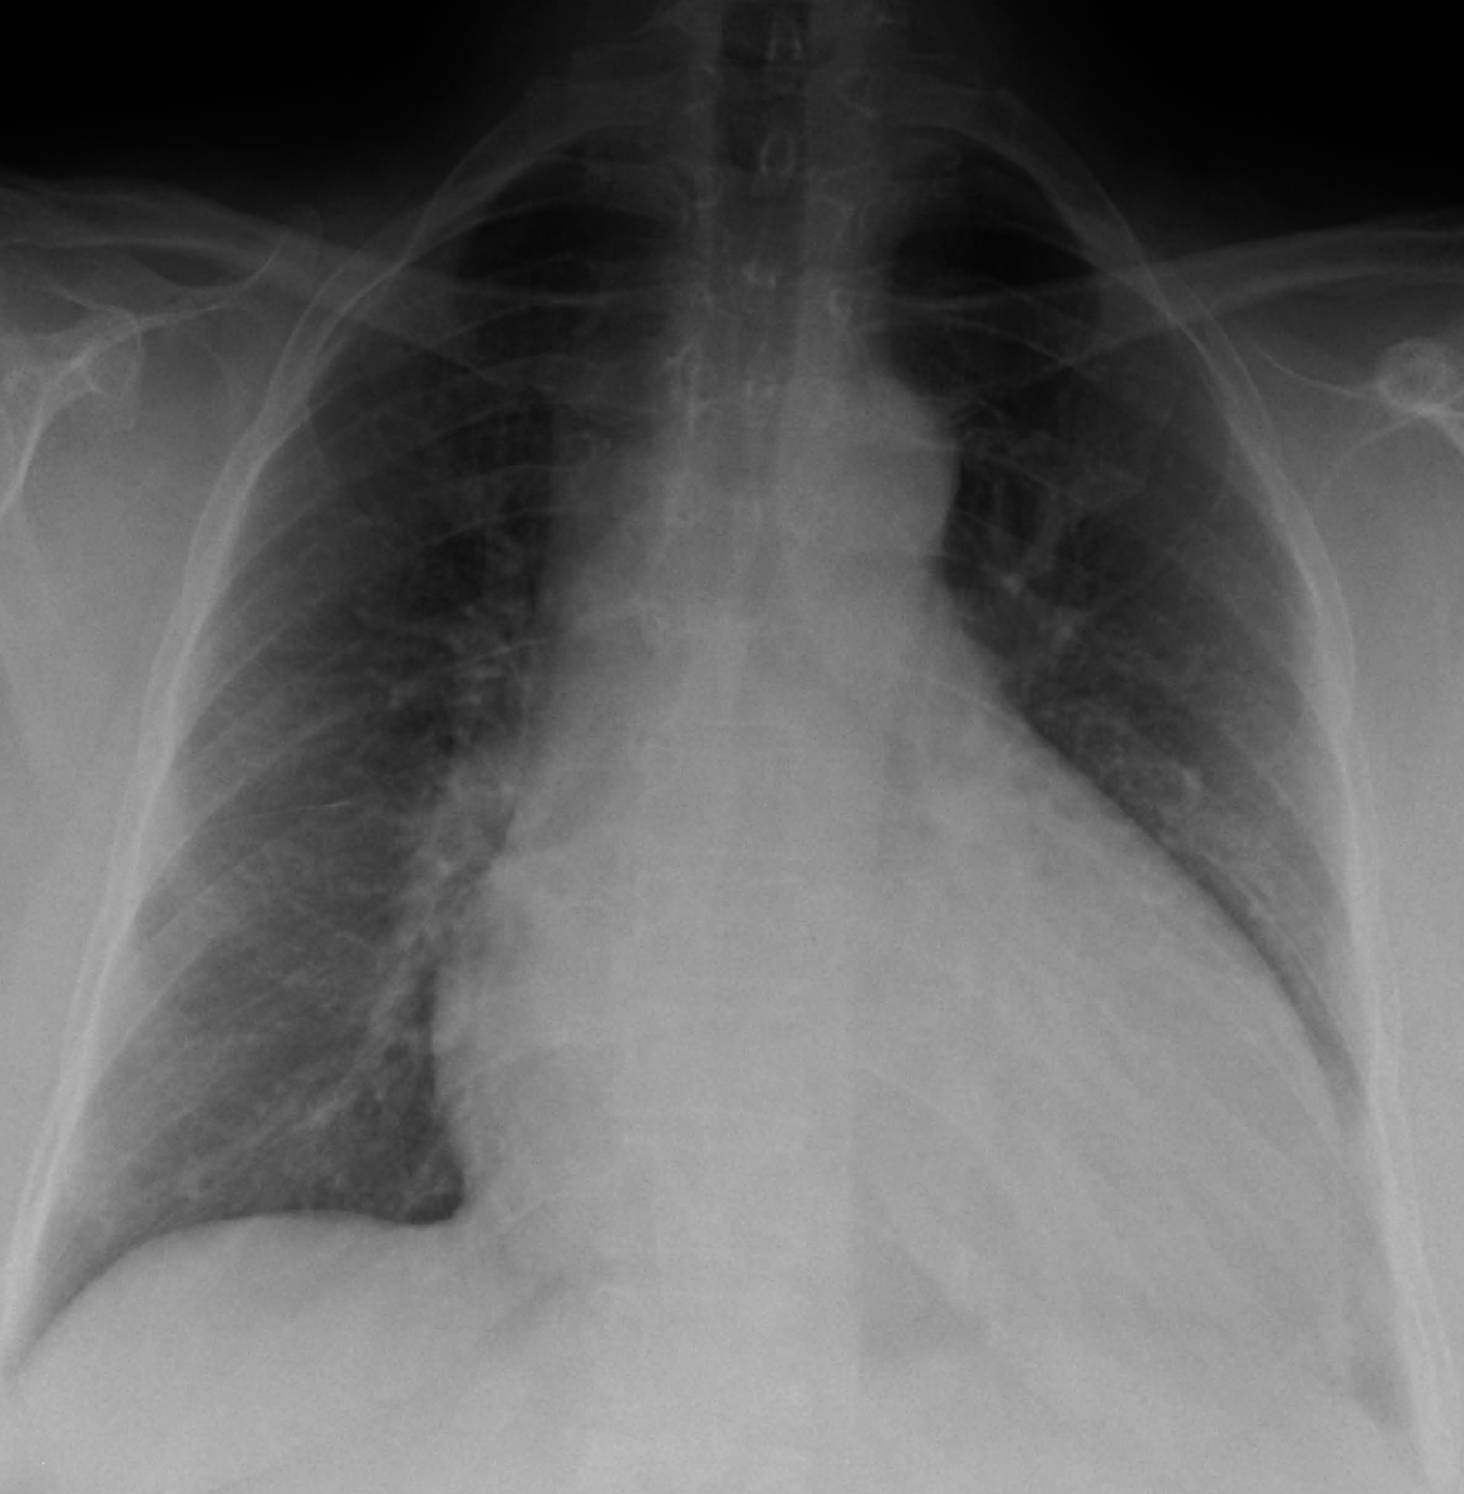

Dilated cardiomyopathy (DCM) is a type of heart muscle disease characterized by the enlargement and weakening of the heart’s main pumping chamber, the left ventricle. This progressive condition impairs the heart’s ability to pump blood efficiently to the rest of the body, leading to symptoms of heart failure. A chest X-ray, as depicted here, is often one of the initial diagnostic tools used to identify significant cardiac enlargement, a key indicator of DCM. While not definitive on its own, a CXR provides valuable clues that prompt further, more specific investigations.

The image vividly demonstrates the hallmark features of dilated cardiomyopathy: an enlarged cardiac silhouette. This enlargement is a direct consequence of the ventricular dilation and thinning of the heart muscle walls that occur in DCM. Understanding these radiological signs is crucial for early detection and for guiding subsequent diagnostic steps, which typically include echocardiography for functional assessment and other advanced imaging or genetic tests to determine the underlying cause.

A chest X-ray in a patient with dilated cardiomyopathy typically reveals several characteristic findings. The most prominent feature, as illustrated in the diagram, is cardiomegaly, which refers to an enlarged heart silhouette. The cardiothoracic ratio (the ratio of the maximum horizontal cardiac diameter to the maximum horizontal thoracic diameter) is often increased, usually exceeding 0.5. The heart appears globular or “pear-shaped” due to the significant dilation of all four cardiac chambers, though the left ventricle is typically the most affected and contributes most to the enlargement seen on a PA (posteroanterior) view.

In addition to cardiomegaly, signs of pulmonary venous hypertension and pulmonary edema may also be evident, reflecting the backward flow of blood due to the heart’s impaired pumping ability. These signs can include:

- Cephalization of pulmonary vessels: The upper lobe pulmonary veins appear engorged as blood is shunted upwards due to increased pressure.

- Kerley B lines: Small, horizontal lines seen at the lung periphery, indicating interstitial edema.

- Pleural effusions: Fluid accumulation in the space between the lungs and the chest wall, often seen as blunting of the costophrenic angles.

While a CXR can provide compelling evidence for DCM, it cannot definitively diagnose the condition or precisely quantify cardiac function. It serves as an excellent screening tool, prompting further diagnostic tests such as echocardiography, which provides detailed images of heart structure and function, including ejection fraction, a critical measure of pumping efficiency.